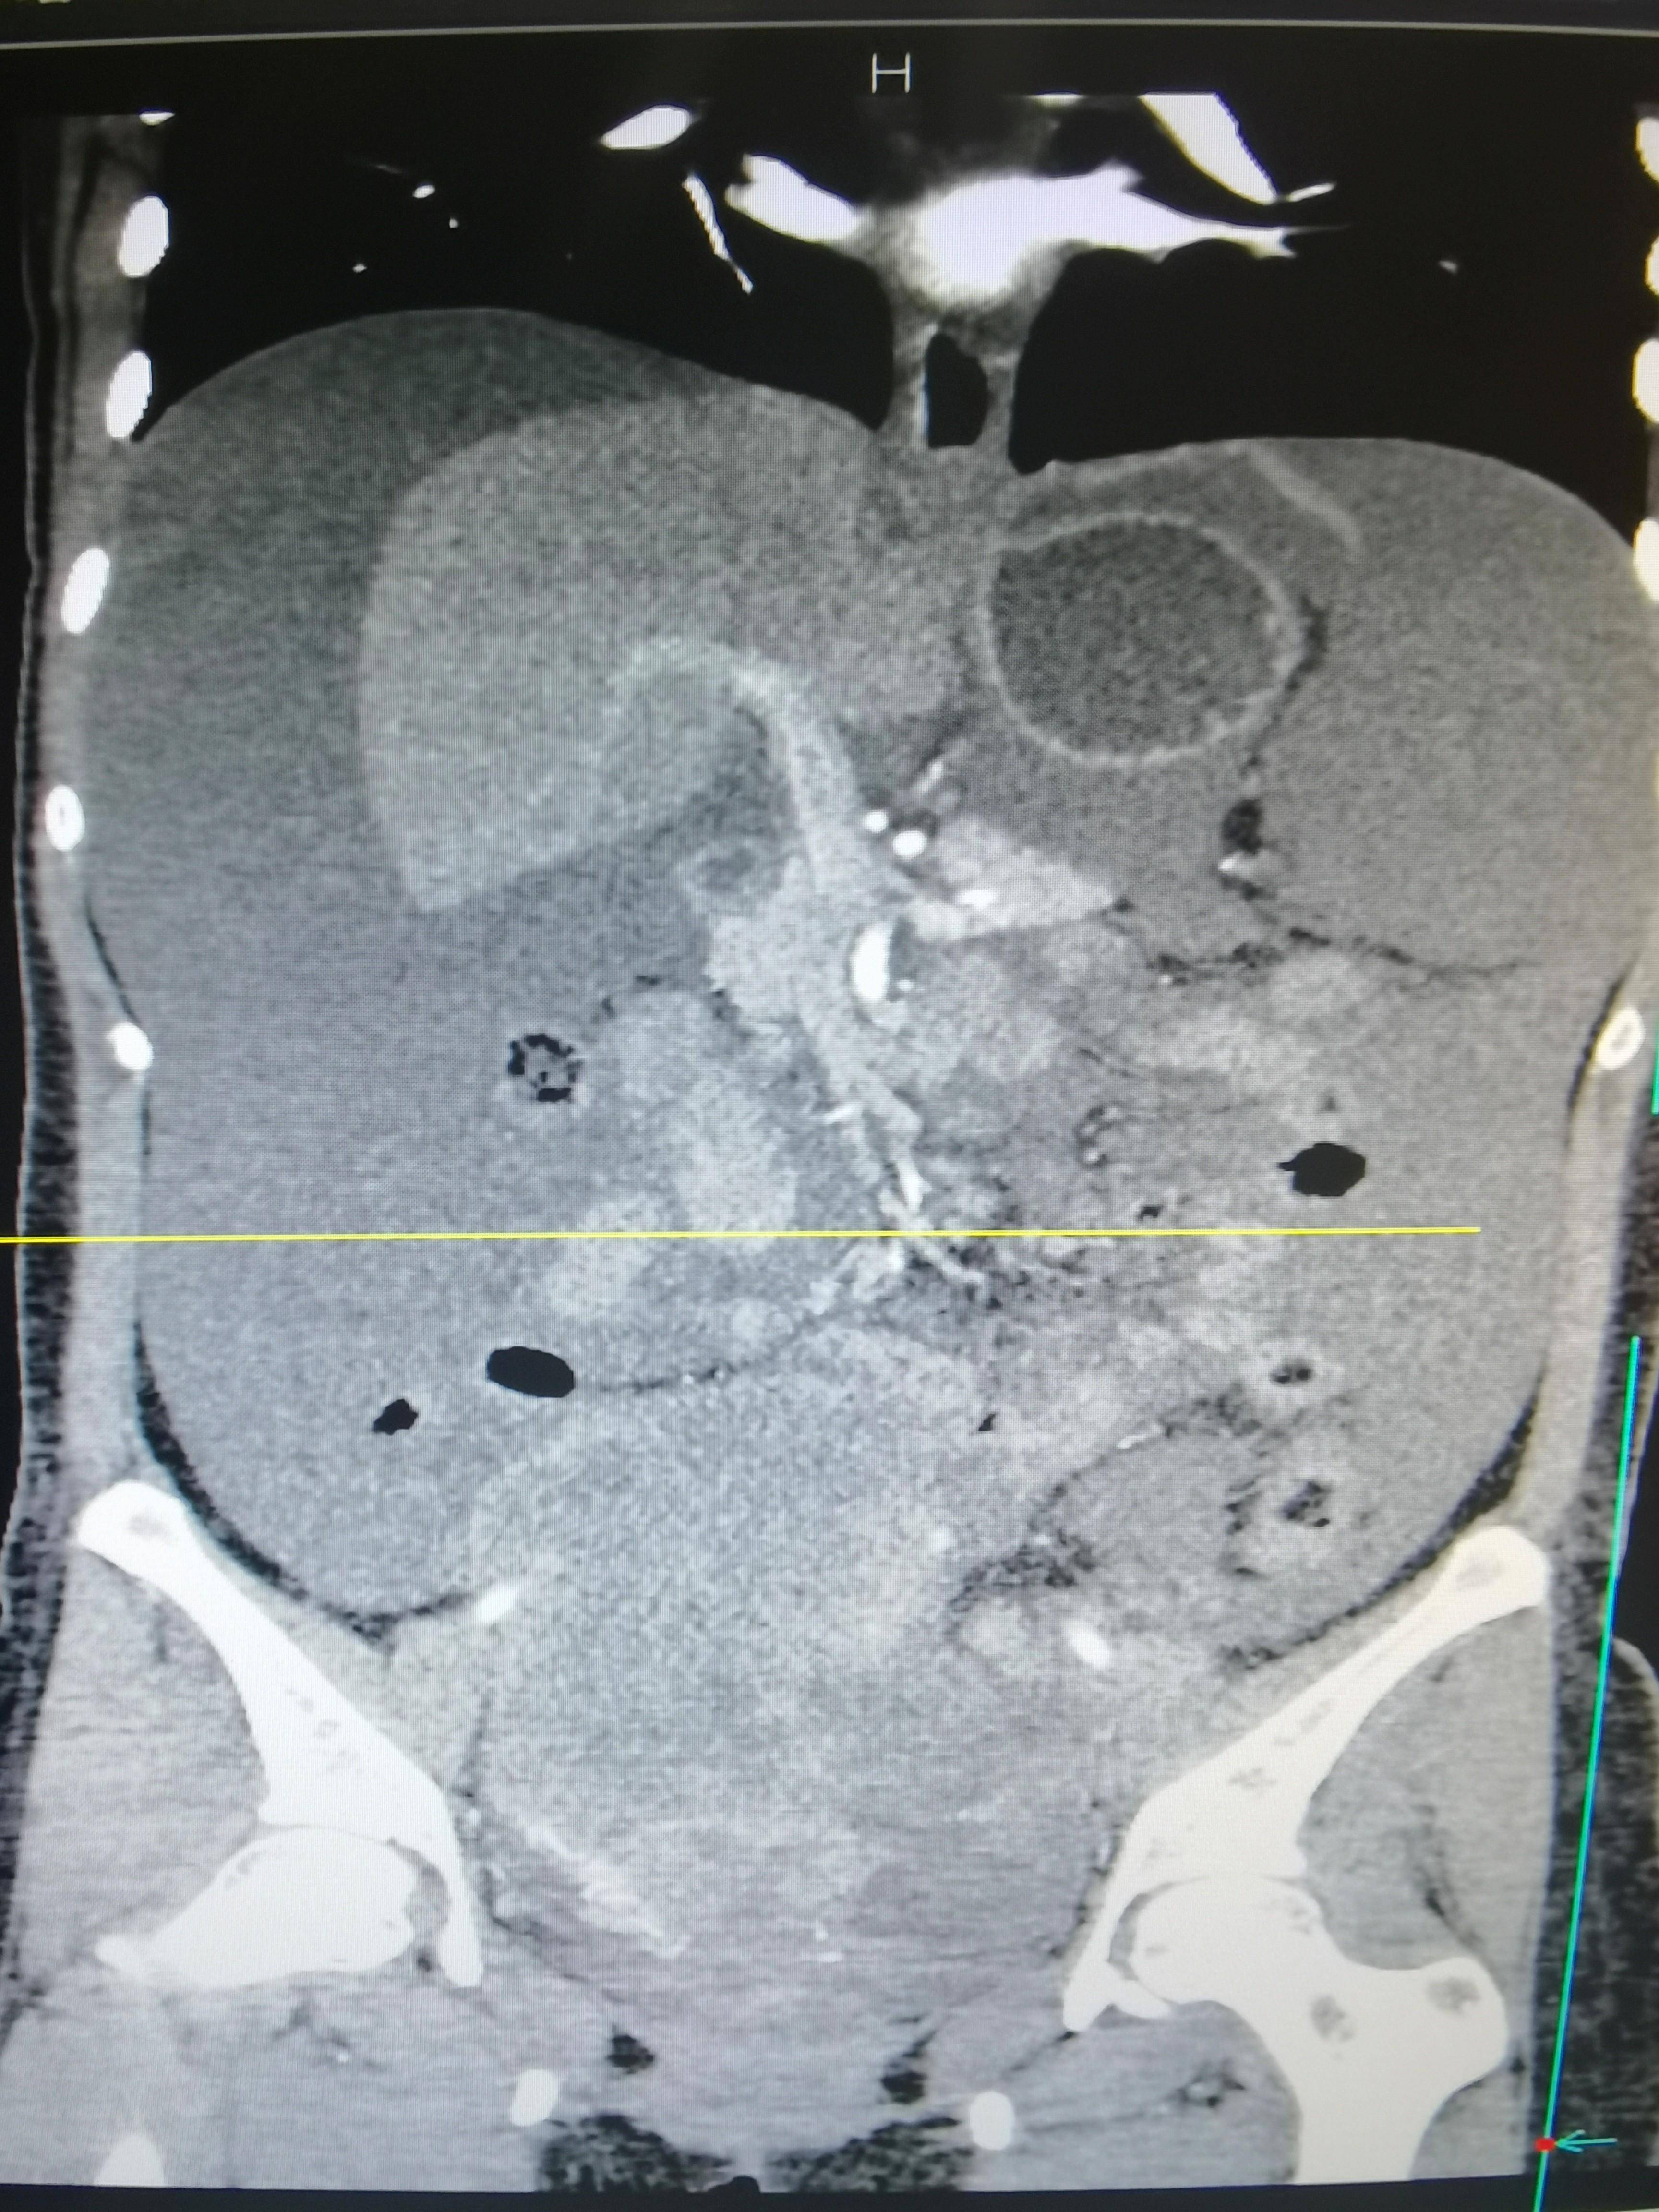

2022年7月15日 腹部CT

◈ 2022年7月15日,行腹部CT检查提示:盆腔见较大不规则形混杂密度影,与双侧附件及邻近肠管、右侧髂血管分界不清,最大层面约12.4cm×8.8cm,病变上下径约14.9cm,三期CT值约为28Hu、27Hu、31Hu,其内密度不均,可见片状高密度影及钙化密度影,病变周围似见稍高密度包膜影。左上腹部小肠旁另见一相同性质肿块,约4.9cm×3.2cm,边缘强化,与局部肠管分界不清。腹腔内见较多液体密度影。网膜略增厚。

◈ 检查诊断:1、盆腔占位病变,对比2022-04-30片体积稍减小、强化减低。2、腹腔积液,对比前片积液量明显增加;网膜略增厚,请结合临床。3、左上腹部小肠占位性病变,请注意复查。

◈ 考虑肿瘤进展(PD),并且左上腹部小肠占位,考虑转移,腹水量增大。